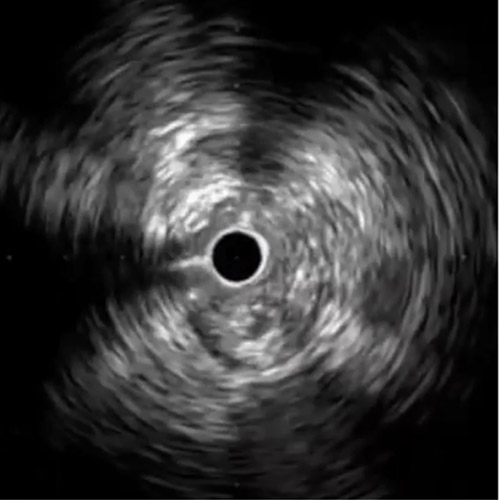

ATA入口部を先端アングルタイプのマイクロカテーテルと3gワイヤーで捉えたが、ATAの途中からワイヤーがとぐろを巻き進まなくなったのでIVUS(AnteOwl WR™)ガイドワイヤリングに切り替えた(図3)。ATA-MIDからSubに迷入していることを確認し(図4)、IVUSガイドで12gワイヤーをプラーク内に誘導しトラッキング出来た。最後DAの屈曲部分にIVUSもワイヤーも追従しなかったので再び3gワイヤーにステップダウンしワイヤーをCTO出口に誘導した。

症例の流れ:IVUS観察下でのTrans Pedal Approach

DAにマイクロカテーテルを進め造影をするとPlanter Arteryを確認出来たので(図5)、潰瘍の状態と血管開存を考えるとPTA(Posterior Tibial Artery)-Planter方向の血流を確保するのが良いと考えTrans Pedal Approachを行った。ATA-DAをballooningしマイクロカテーテルを追従させ、難渋しながらも1gワイヤーが進んだが進行方向は内側であり違和感を覚えた(図6)。確認のためIVUS(AnteOwl WR™)観察下でTrans Pedal Approachを行い(図7)、ワイヤーはTrueルーメンにあることを確認した(図8)。PA-Planterのvariant typeと判断し、アンテグレードからPAをワイヤリングすることでランデブーに成功した。その後、3㎜でballooningし終了した(図9)。AnteOwl WR™観察下でATAを順行性にワイヤー通過出来たこと、そしてAnteOwl WR™をPedal Arteryに追従させレトロワイヤーの状況を確認出来たことが手技成功のポイントであった。